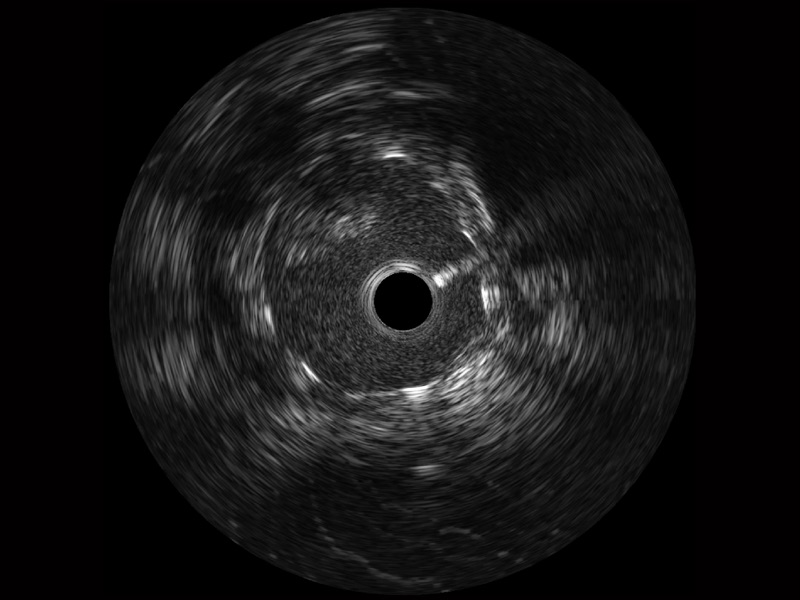

传统IVUS图像

对比传统IVUS导管成像,db真人体育官网宽频IVUS图像的近场支架梁显影更细腻,远场中膜外血管仍清晰可辨,兼顾远中近,兼顾分辨力与穿透深度